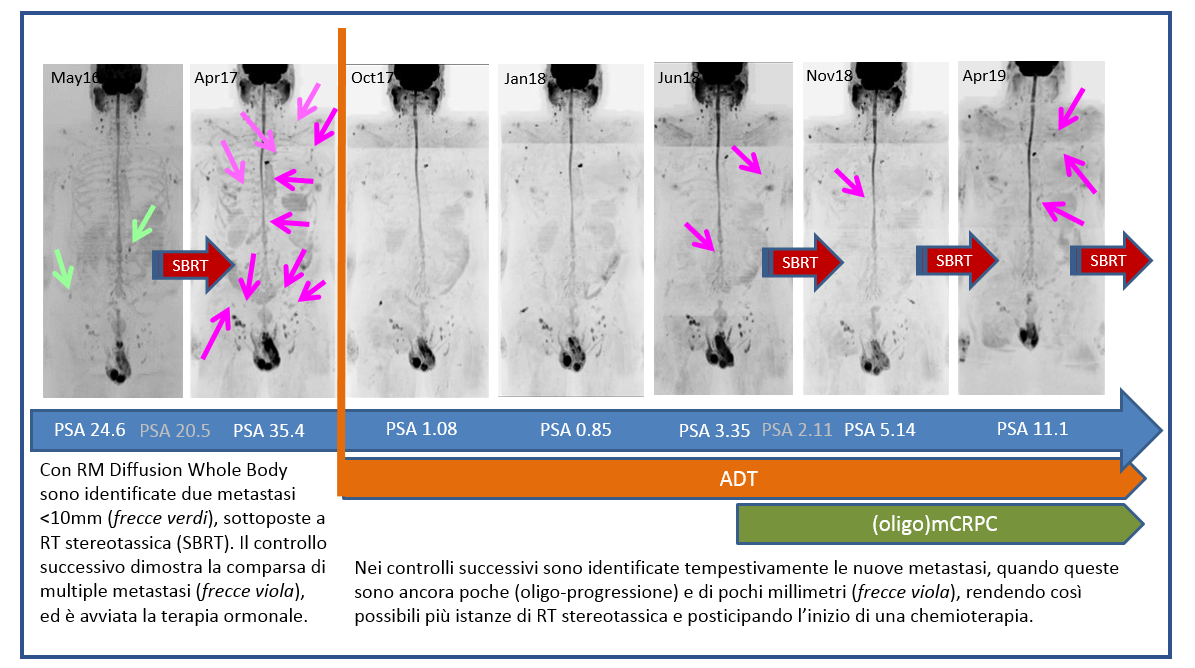

Le tecniche di imaging funzionale permettono di studiare non solo la morfologia delle lesioni tumorali, ma anche le loro caratteristiche funzionali, come ad esempio la densità cellulare, la perfusione e il metabolismo. L’integrazione dell’imaging funzionale con i parametri clinici e altri biomarcatori del singolo paziente prende il nome di “imaging di precisione”.

Grazie all’imaging di precisione è possibile valutare in maniera più accurata la presenza di un tumore, la sua estensione e l’efficacia delle terapie somministrate, allo scopo di rendere personalizzata la cura oncologica, in relazione alle esigenze del singolo paziente.

Imaging di precisione: caso 3